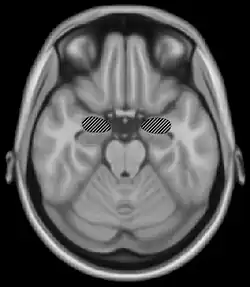

Basal ganglia and motor memory

The basal ganglia are a group of nuclei which are located in the medial temporal lobe, above the thalamus and connected to the cerebral cortex. Specifically, the basal ganglia includes the subthalamic nucleus, substantia nigra, the globus pallidus, the ventral striatum and the dorsal striatum, which consists of the putamen and the caudate nucleus.[8] The basic functions of these nuclei deal with cognition, learning, and motor control and activities. The basal ganglia are also associated with learning, memory, and unconscious memory processes, such as motor skills and implicit memory.[4] Particularly, one division within the ventral striatum, the nucleus accumbens core, is involved in the consolidation, retrieval and reconsolidation of drug memory.[9]